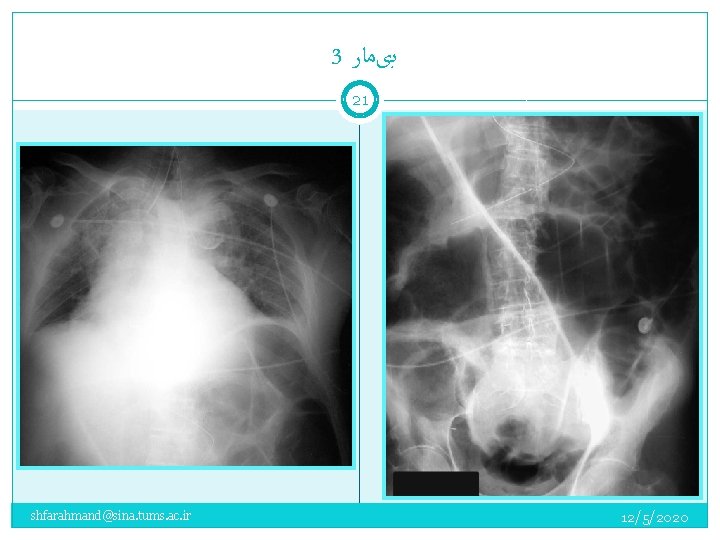

3 ﺑیﻤﺎﺭ 20 An 83 -year-old man was brought to the ED by ambulance for progressive shortness of breath of one day duration. On arrival, he was in severe respiratory distress and was unable to provide a detailed medical history. On examination: Vital signs: BP: 150/80 mm Hg PR: 120/min, irregular RR: 36/min; pulse oximetry SO 2 78% on room air. There was poor air movement bilaterally. His abdomen was distended, tympanitic to percussion, and non-tender. Bowel sounds were quiet, but present. The patient stated that he had been constipated for six days, but had a bowel movement the previous day. On 100% oxygen by face mask, the pulse oximetry SO 2 was 92%. ABG: p. H 7. 20, PCO 2 59 mm Hg, 79 mm Hg, PO 2 79 mm Hg The patient was intubated. shfarahmand@sina. tums. ac. ir 12/5/2020

3 ﺑیﻤﺎﺭ 21 shfarahmand@sina. tums. ac. ir 12/5/2020